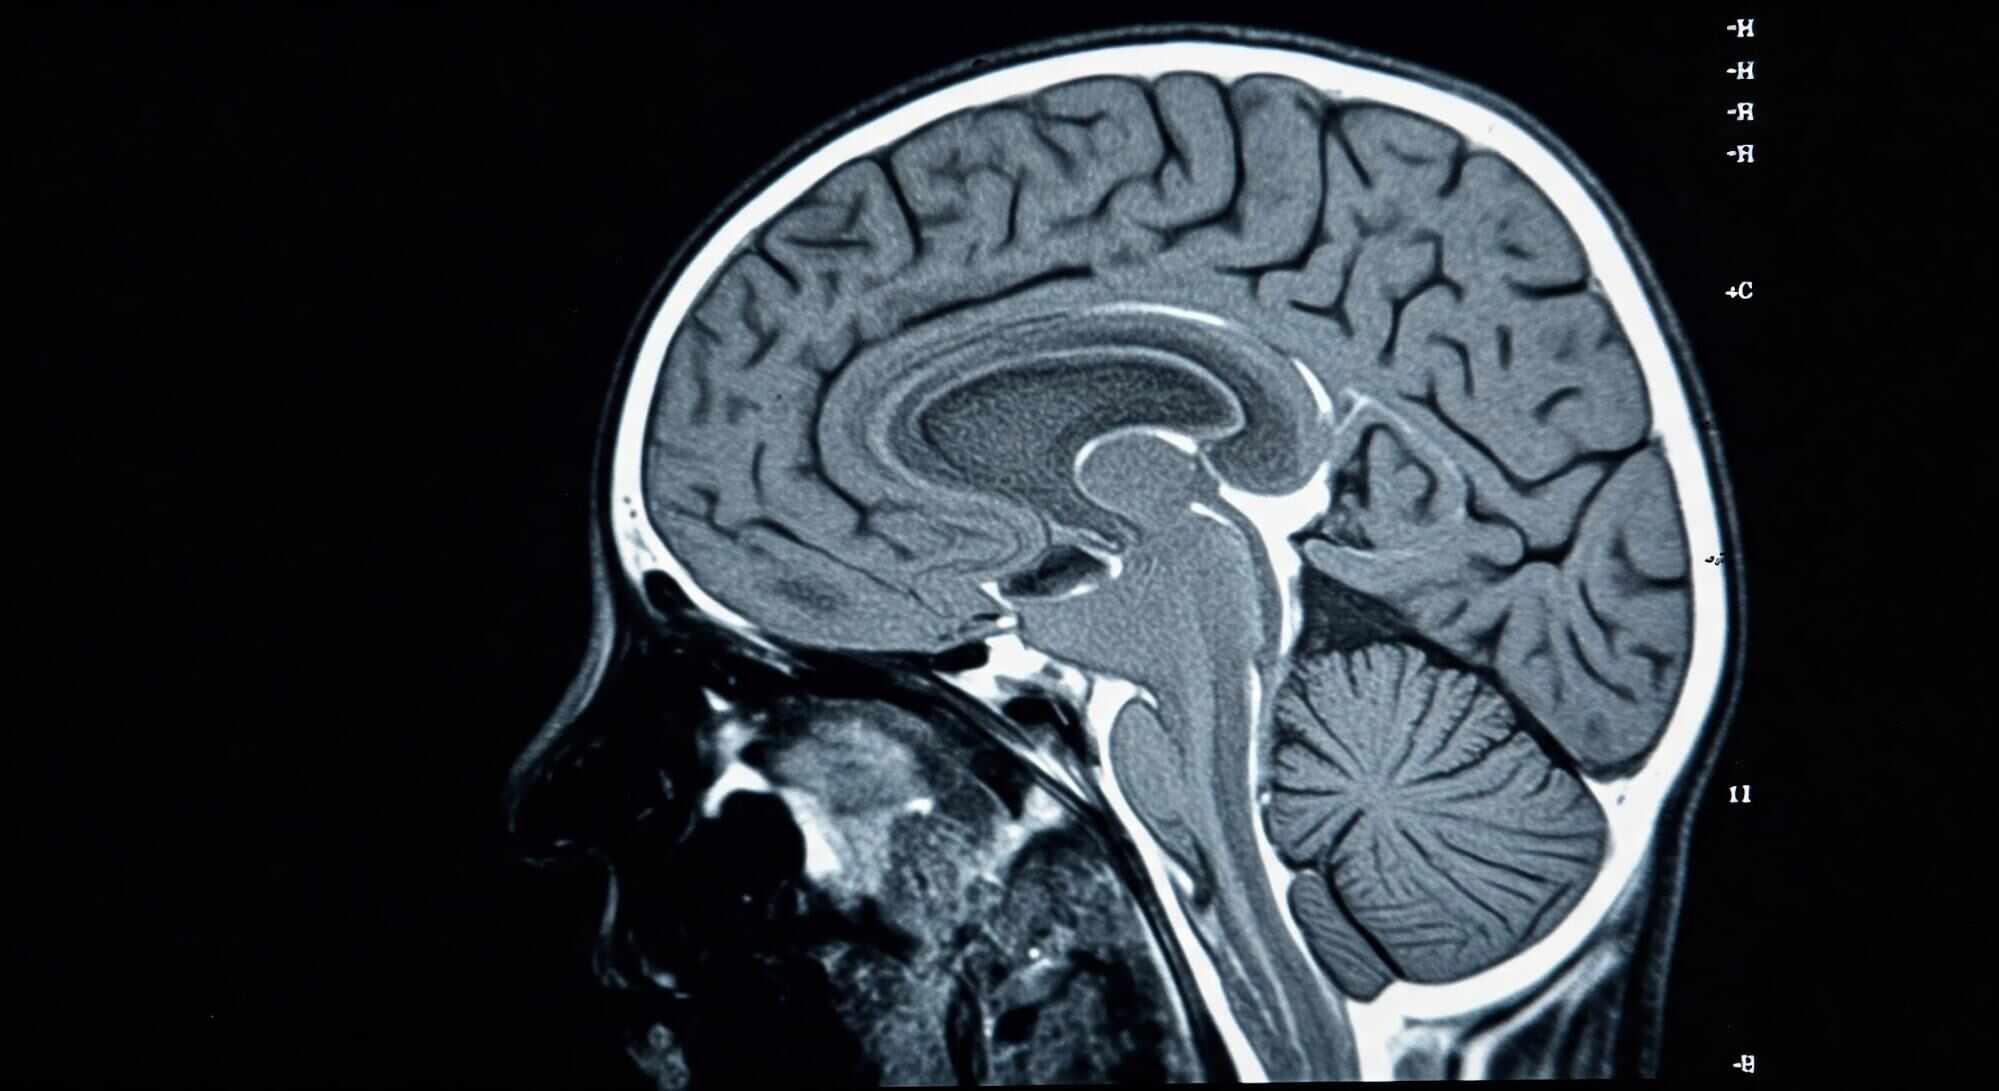

Workplace Traumatic Brain Injury Injuries

One minute you’re handling your job like any other day. The next, you’re facing confusion, pain, or memory loss—and your life begins to change in ways you never imagined. These injuries aren’t always obvious, but the impact can be overwhelming. Head trauma can silently affect your ability to work, think clearly, connect with your loved ones, and manage everyday tasks.

The consequences of a traumatic brain injury extend far beyond the initial blow. While some effects are immediate, others take time to surface and can alter the course of your life in unexpected ways. What may seem like a minor incident can gradually lead to significant cognitive, emotional, and physical challenges that impact your independence, relationships, and career.

Traumatic brain injuries are notoriously difficult to recognize in the early stages. Many people dismiss the initial signs—like fatigue, confusion, or headaches—as temporary or unrelated. But even subtle changes in mood, sleep, or focus can indicate something much more serious. The delay in symptoms can make it harder to connect them to the original injury, which is why early medical evaluation is crucial.